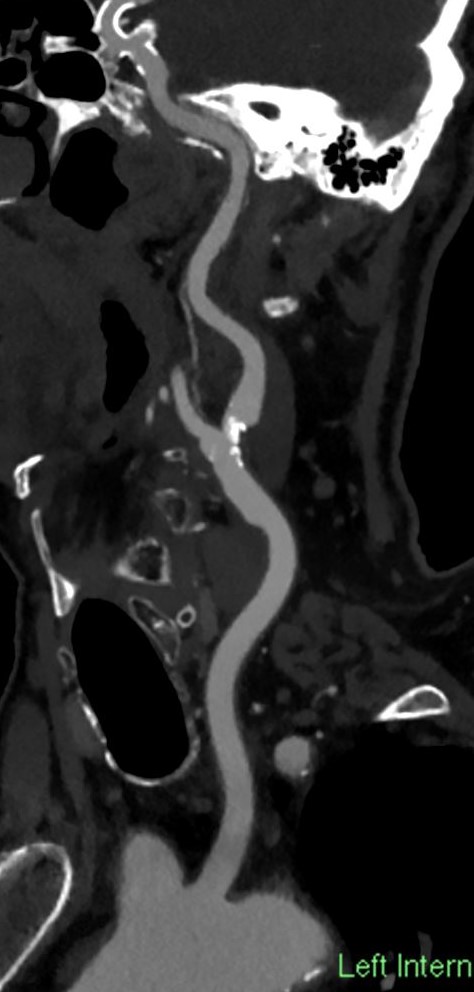

Image

Original axial slice of the CTA

' "Curving" secondary reformatted image following the way of the artery'

Fig. 16., 17. Atherosclerotic plaques in the carotid bifurcation, causing significant stenosis

CTA (if done by multislice - above 64- CT) has the main advantage of showing in detail even highly irregular contoured, unevenly calcified plaques, and the residual lumen so the grade of the stenosis can be measured with more confidence. That is why, nowadays, if there are no contraindications, duplex US is always followed by a CTA, in special cases MRA as an alternative.